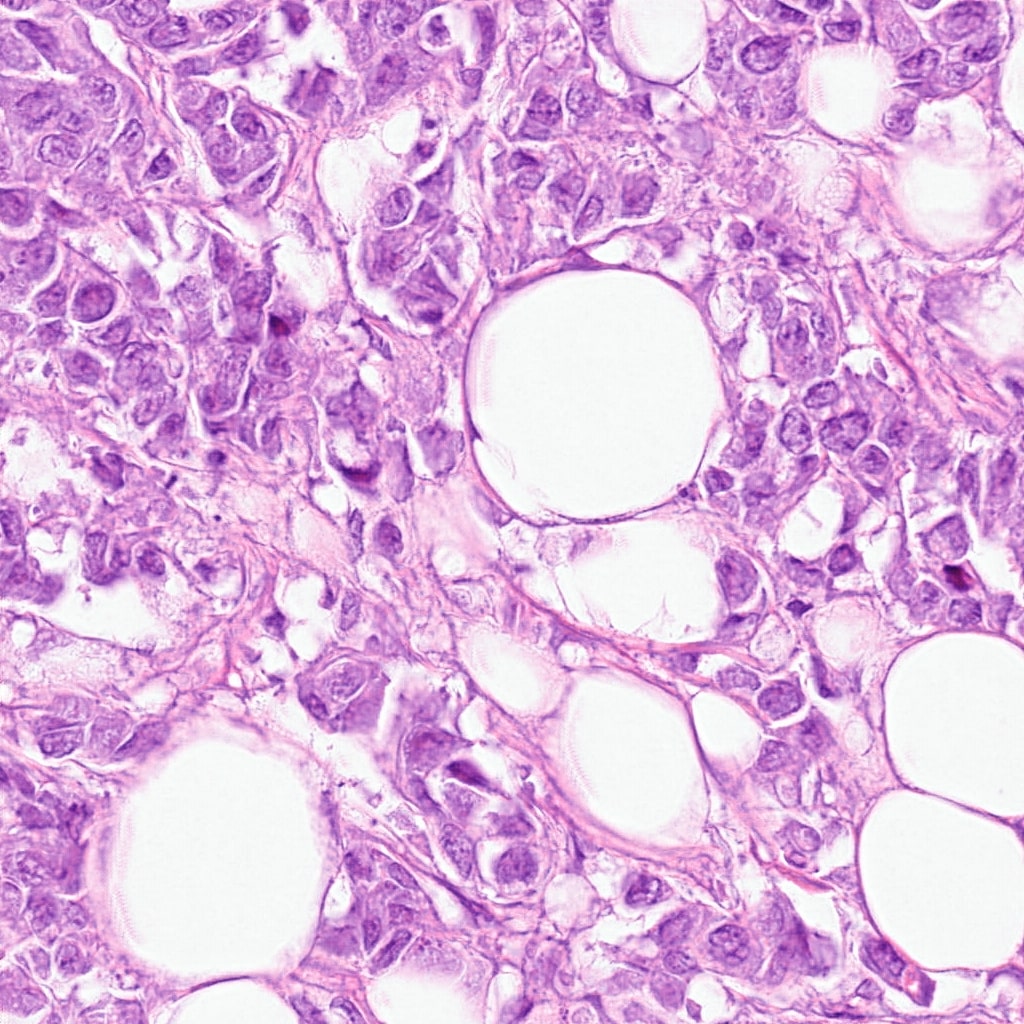

(b) transformed patch for Hamamatsu XR NanoZoomer 2.0

Refer to caption

(c) original patch from Hamamatsu S360

Figure 2: The plots show 1024x1024 patches from original and transformed patches. The domain variability is evident by visual differences in staining in (a), (c), (e), and (f). The transformed patches to the right (b), (d), (f), and (h) respectively shows consistent staining pattern while preserving morphology.